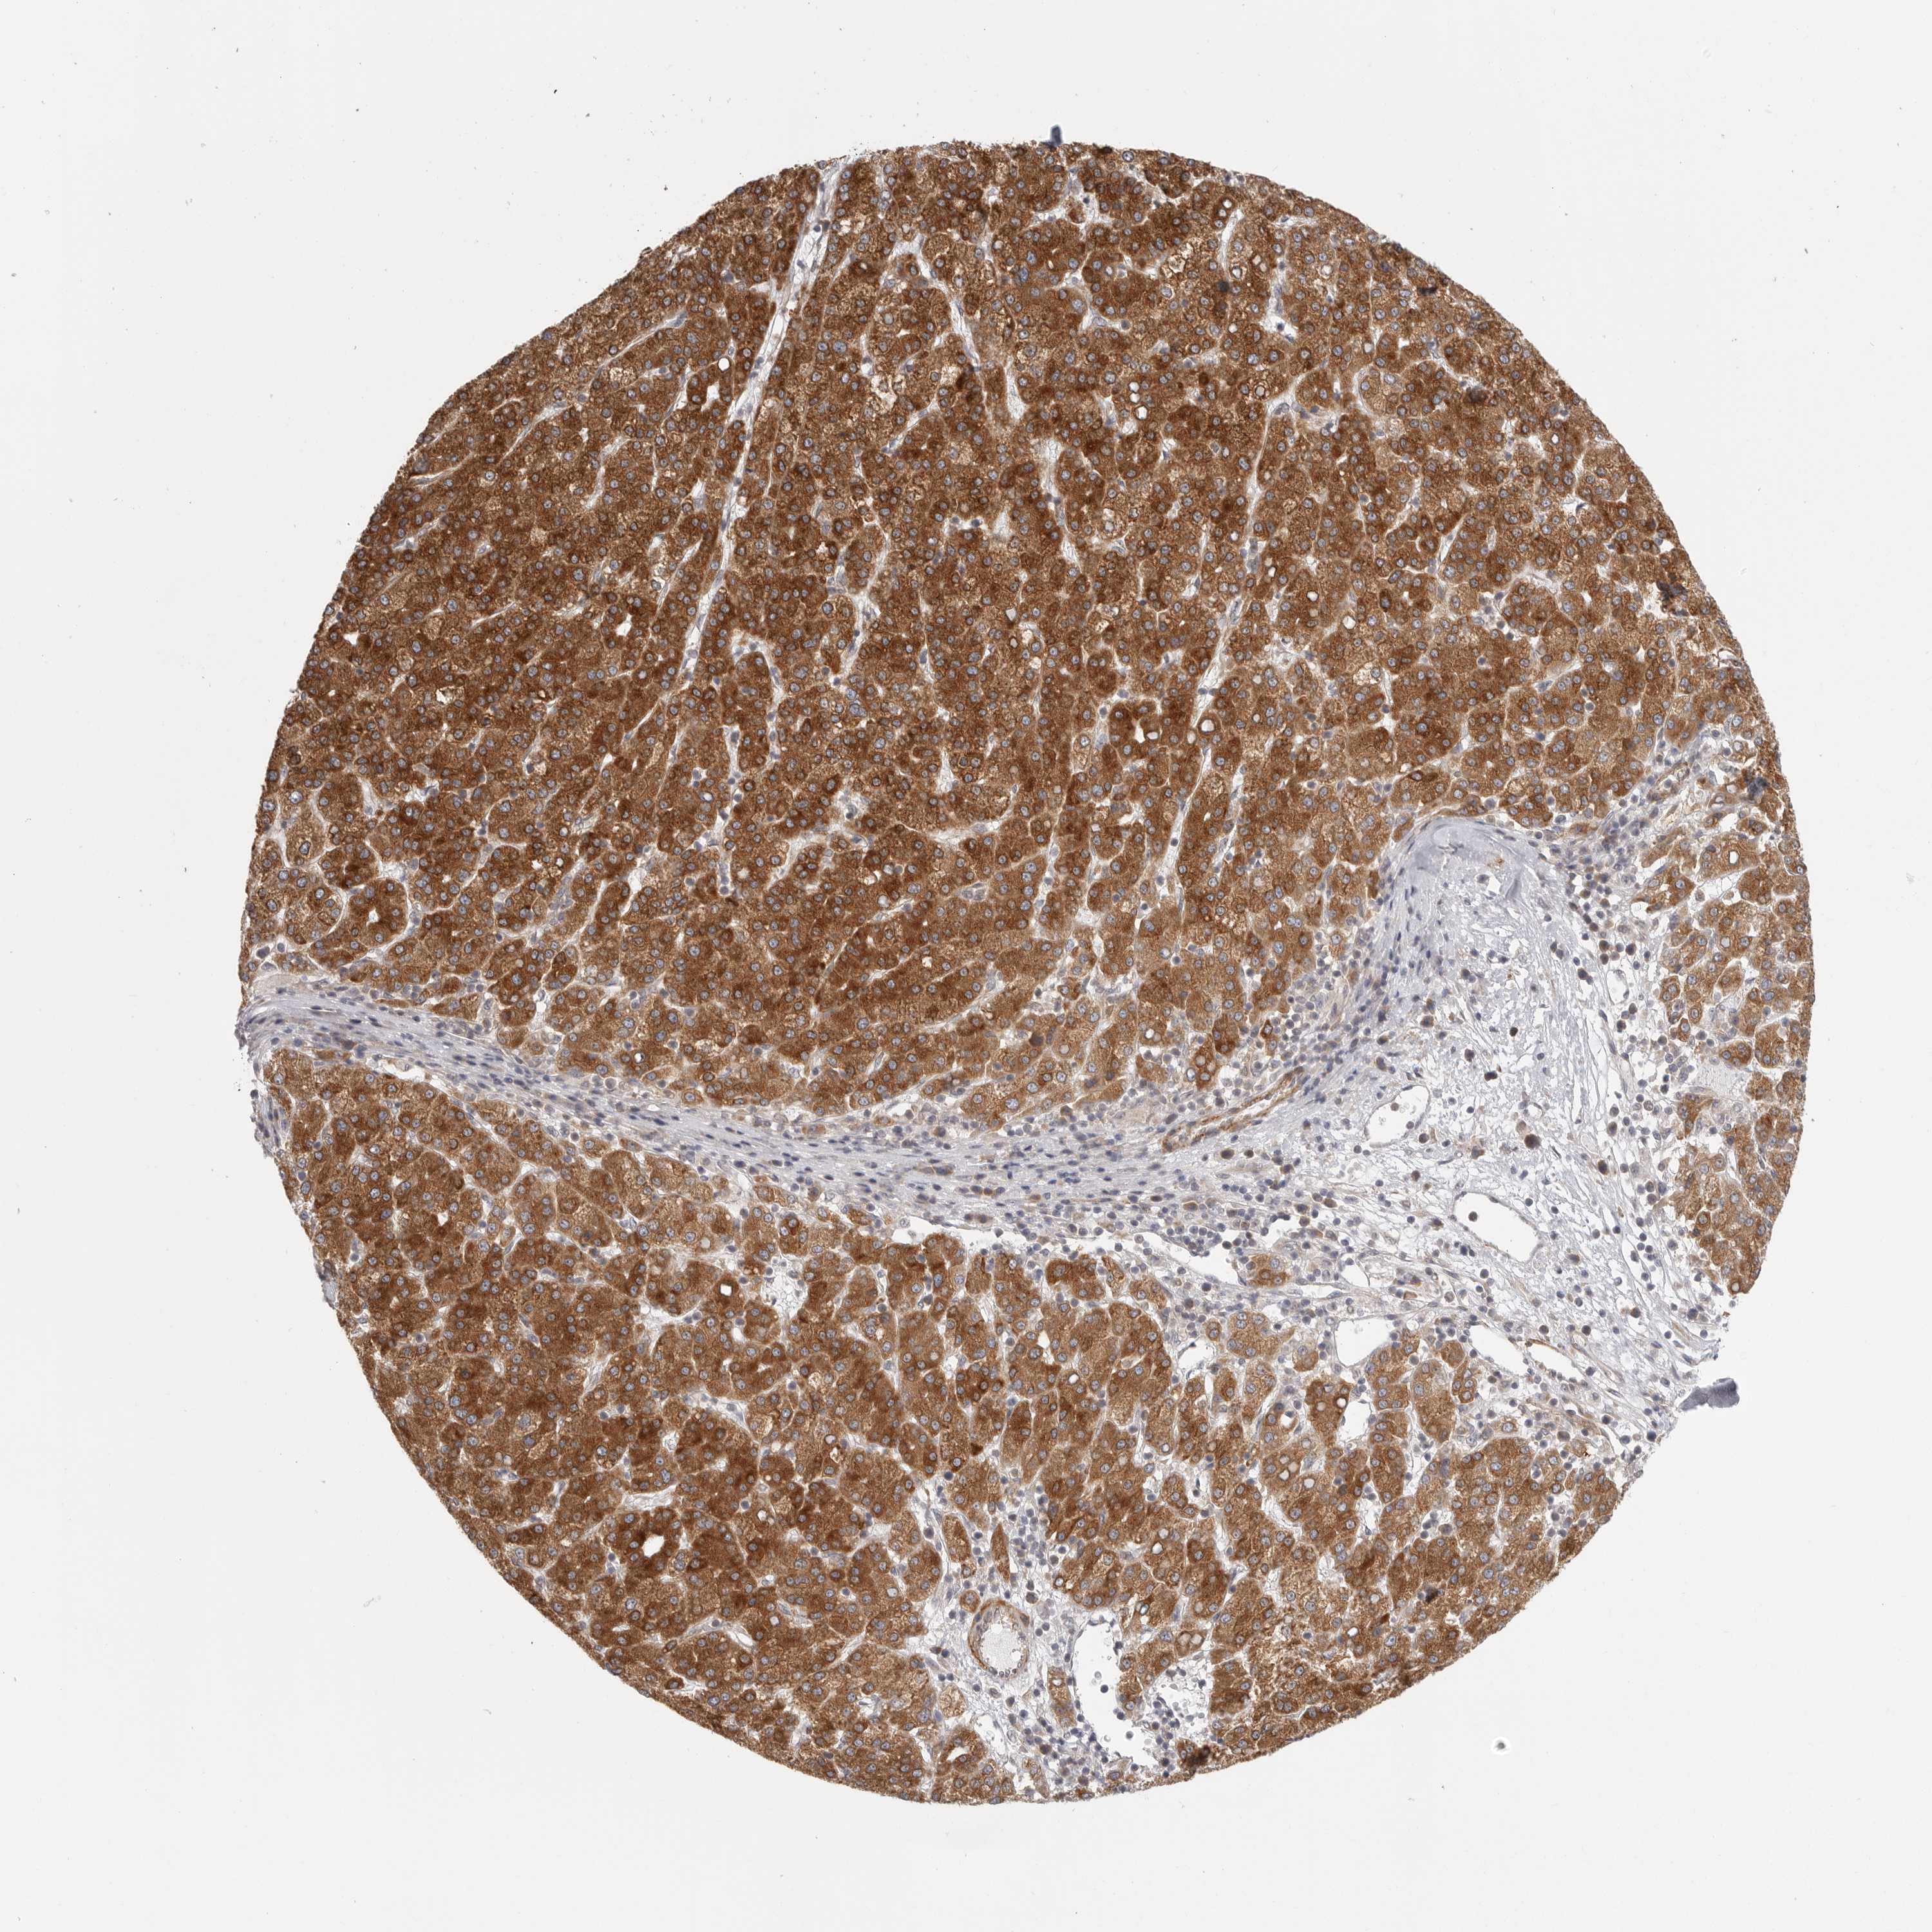

LIVER CANCER - Protein expressioni

A mouse-over function shows sample information and annotation data. Click on an image to view it in a full screen mode. Samples can be filtered based on level of antibody staining by selecting one or several of the following categories: high, medium, low and not detected. The assay and annotation is described here.

Note that samples used for immunohistochemistry by the Human Protein Atlas do not correspond to samples in the TCGA dataset.

Antibody stainingi

Antibody staining in the annotated cell types in the current human tissue is reported as not detected, low, medium, or high, based on conventional immunohistochemistry profiling in selected tissues. This score is based on the combination of the staining intensity and fraction of stained cells.

Each image is clickable and will lead to virtual microscopy that enables deeper exploration of all samples and also displays staining intensity scores, fraction scores and subcellular localization as well as patient and tissue information for each sample.

Antibody HPA027262

Antibody HPA078737

Cholangiocarcinoma

Carcinoma, Hepatocellular, NOS